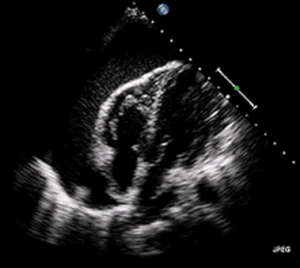

| A 2D transthoracic echocardiogram of pericardial effusion. The "swinging" heart | |